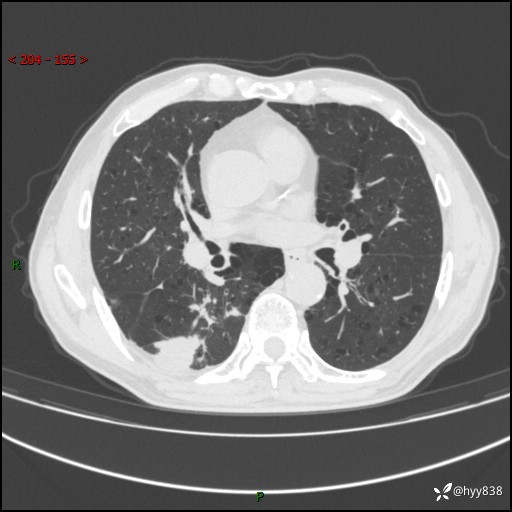

老年男性,发现右下肺结节3天。结节+卫星灶,似曾相识---结果公布~

简要病史:患者3天前于我院常规体检时行胸部CT提示“右下肺结节35mm*24mm”,自觉无发热、咳嗽、咳痰,无胸痛、咯血、气促加重,无声嘶、吞咽困难,无乏力、盗汗、体重减轻等不适。为求进一步诊治,入我院求诊,门诊以“右下肺结节待查”收入我科。患者3天前于我院常规体检时行胸部CT提示“右下肺结节35mm*24mm”,自觉无发热、咳嗽、咳痰,无胸痛、咯血、气促加重,无声嘶、吞咽困难,无乏力、盗汗、体重减轻等不适。为求进一步诊治,入我院求诊,门诊以“右下肺结节待查”收入我科。 起病以来,患者精神、食欲、睡眠可,体力稍差,大小便正常,体重无明显变化。

辅助检查:CT

胸部CT平扫